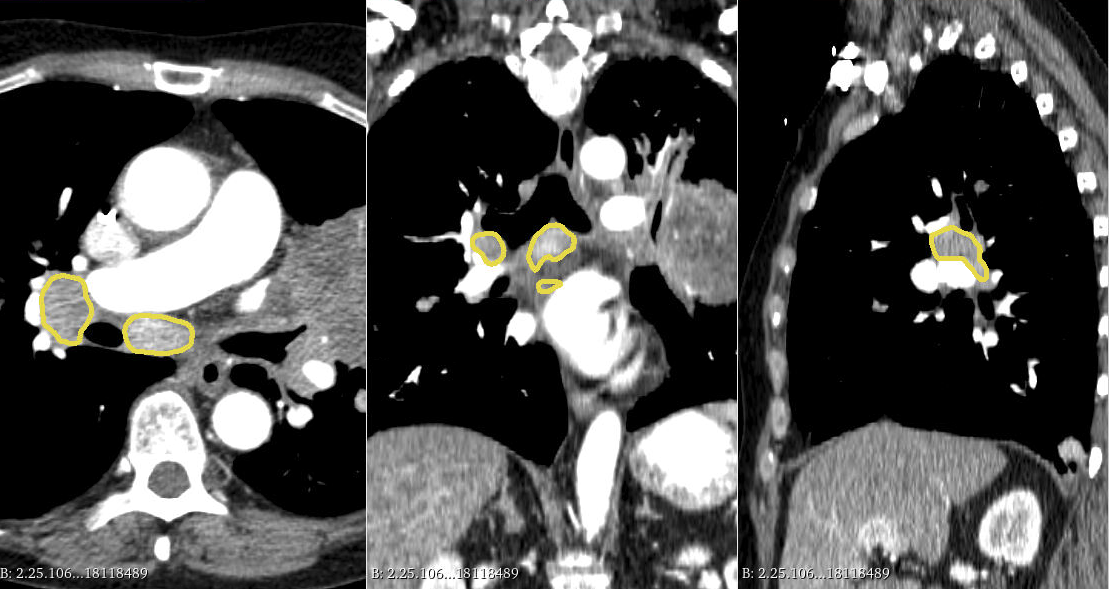

Example of expert annotations of mediastinal lymph nodes on a contrast-enhanced CT scan of the type to be used in the challenge.